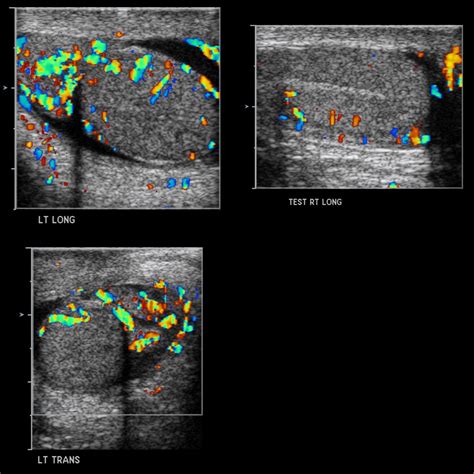

• Scrotal Ultrasound: This is the most common diagnostic tool. It uses sound waves to create images of the scrotum, allowing doctors to visualize blood flow, detect tumors, identify varicoceles, or confirm torsion.